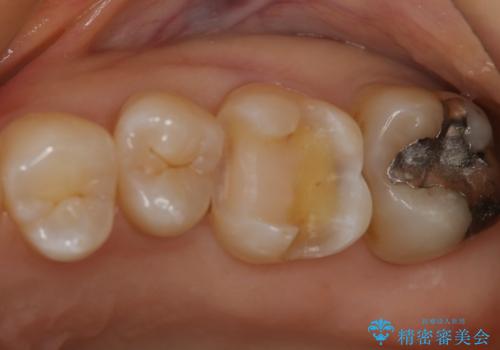

- 左上6番の銀歯をセラミックにしたいと希望され来院された患者様です。

切削量を考慮し、セラミックインレーを選択しました。

銀歯を除去したところ虫歯が深かったので、CRを詰めた上で形態を整えています。